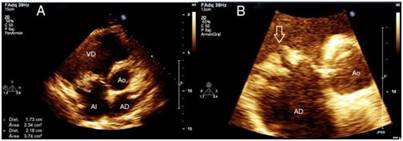

En el examen físico se detectaron los siguientes datos positivos: peso: 83 kg, talla: 1,76 m y un índice de masa corporal de 26.79 kg/m2. Temperatura axilar de 39.2 ◦C. En la región del cuello se observó una distensión venosa yugular con una onda sistólica prominente. En el sistema cardiovascular se ausculta un soplo sistólico iii/vi de mayor intensidad en el 4.◦ espacio intercostal paraesternal izquierdo y la región subxifoidea, con un aumento de intensidad durante la inspiración, una presión arterial de 110/80 mmHg y una frecuencia cardíaca de 97 latidos por minuto. En el abdomen se advirtió la presencia de una hepatomegalia de alrededor 1 cm por debajo del reborde costal, de consistencia firme, no dolorosa. Tejido celular subcutáneo infiltrado en ambos miembros inferiores hasta 1/3 inferior tibial de fácil godet. Como parte de los análisis de laboratorio realizados, se reportó una leucocitosis ligera con desviación a la izquierda. Velocidad de eritrosedimentación de 96 mm/h. PCR, positiva. Factor reumatoideo, positivo. Serología VIH, negativa. Se realizó un ecocardiograma transtorácico (ETT) (figs. 1 y 2), donde se apreció una imagen ecogénica en la valva anterior de la tricúspide, compatible con vegetación mayor de 17 × 21 mm que generaba déficit en la coaptación valvular con insuficiencia de la misma, además de una disfunción sistólica del ventrículo derecho con un TAPSE de 8 mm y un ventrículo derecho de 41 mm en su base, con des- plazamiento del tabique interventricular hacia la izquierda. Aurícula derecha dilatada, con desplazamiento del septum interauricular hacia la izquierda. Flujo pulmonar con un tiempo de aceleración de 95 ms y una presión media de la arteria pulmonar de 32 mmHg. Se confirmaron hallazgos a través de ecocardiograma transesofágico (ETE), realizado sin complicaciones.

Figura 1: Ecocardiograma transtorácico. Plano paraesternal eje corto o transversal a nivel de los grandes vasos. A) Aurícula derecha (AD), aurícula izquierda (AI), ventrículo derecho (VD), válvula aórtica (Ao), imagen ecogénica en la valva anterior de la tricúspide, compatible con vegetación mayor de 17 × 21 mm). B) Ampliación del aparato valvular tricúspide donde se observan imágenes ecogénicas en ambas valvas, siendo la mayor la observada en valva anterior.